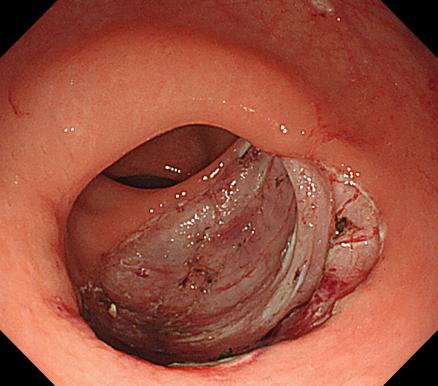

e30e4938ed50461782b5c3b8d31c9d5e.Jpeg6b6cfafe8e7b451095152f7345daa777.Jpeg

胃底靜脈曲張               內鏡下組織膠粘合術

胃底靜脈曲張組織膠粘合術(HI):治療胃底食管靜脈曲張,防止靜脈曲張破裂出血,降低因肝硬化導致胃底靜脈曲張破裂引起的致命風險。